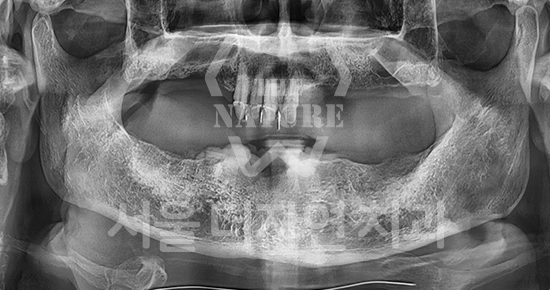

#Full Mouth Implants

-

BEFORE: 2022.12.15

AFTER: 2023.02.23

Treatment outcomes may vary by patient,

and side effects may occur.

These images were taken under the same conditions,

and were published with the patient's consent.